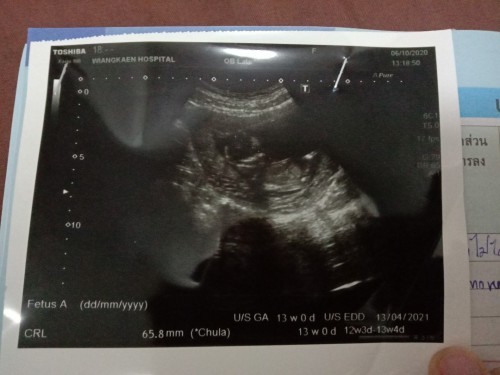

สอบถาม13สัปดาห์

ขอสอบถาม 13สัปดาห์แล้วน้องยังไม่เป็นตัว คนอื่นเป็นเหมือนกันไหมคะ แต่หมอบอกหัวใจน้องเต้น กังวลคะ จะเป็นไรไหม

ตอน13w ตอนนี้23w1